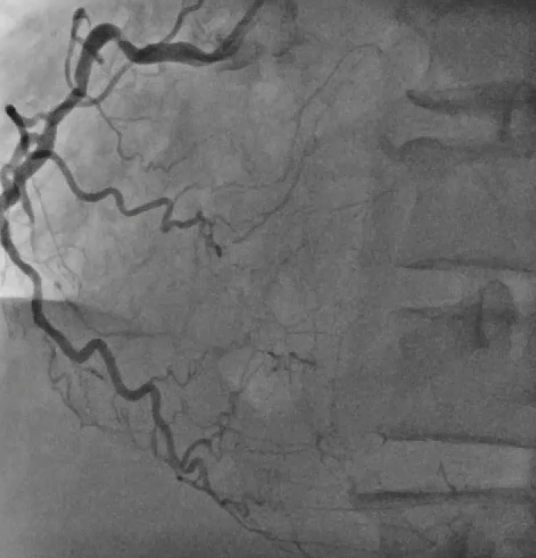

Coronary angiogram showed CTO in all 3 vessels. Impella assisted PCI was suggested in combined HEART team meeting in view of high surgical risk (STS score >8). Antegrade approach was adapted. LAD CTO was successfully crossed with Gaia Next 1 with Turnpike support. A 2.25x40mm stent was deployed to mid LAD and an overlapping 3.5x28mm stent was deployed to LM-LAD across wire protected LCx. Post dilatation was performed. Final IVUS and angiogram showed satisfactory result.